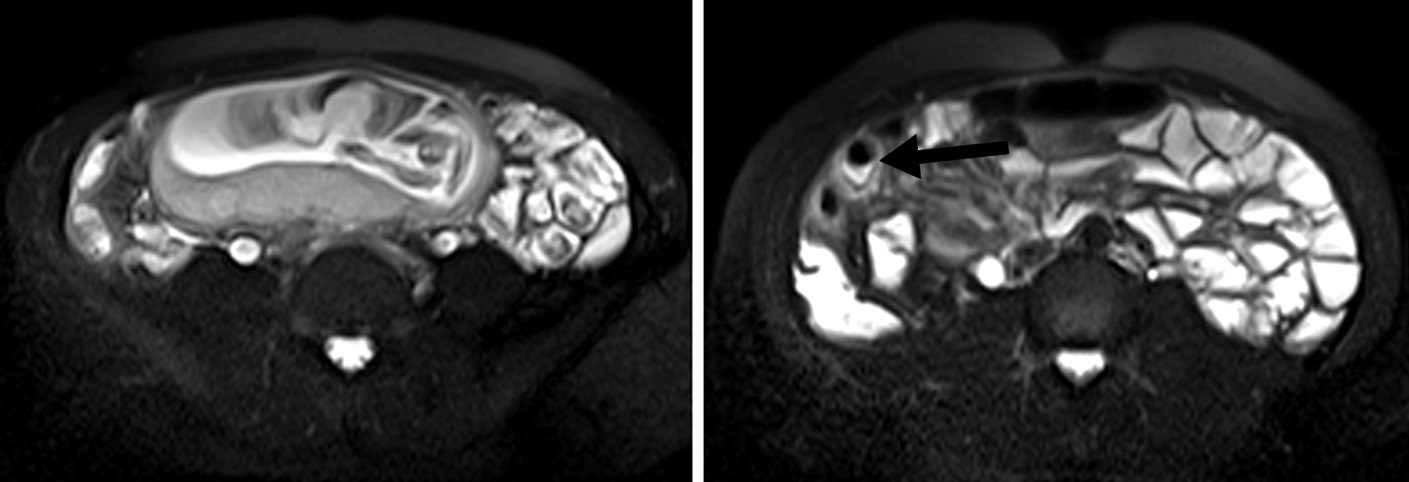

Figura 3

Enfermedad de Crohn

a) Secuencia T2 axial sin

supresión grasa evidencia

engrosamiento parietal de la

última asa ileal (flecha blanca).

b y c) secuencias T1 con

saturación grasa y gadolinio.

Realce estrajpgicado dado

por realce de la mucosa

(flecha larga) y serosa (flecha

corta) separadas por la

capa submucosa edematosa

(asterisco).